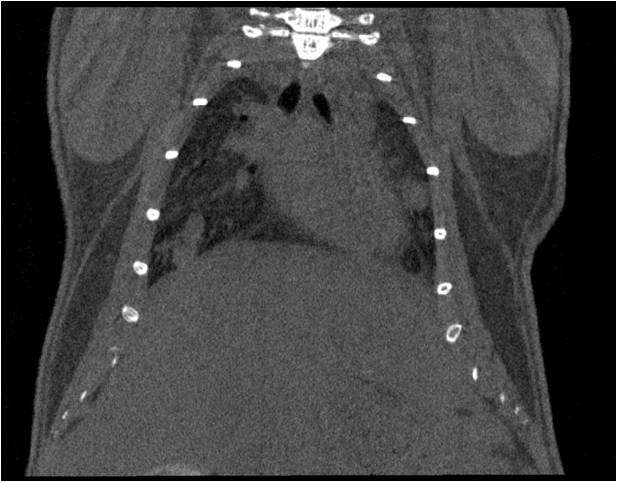

心血管

胸部和心血管的層析成像 胸部和心血管的3D圖像